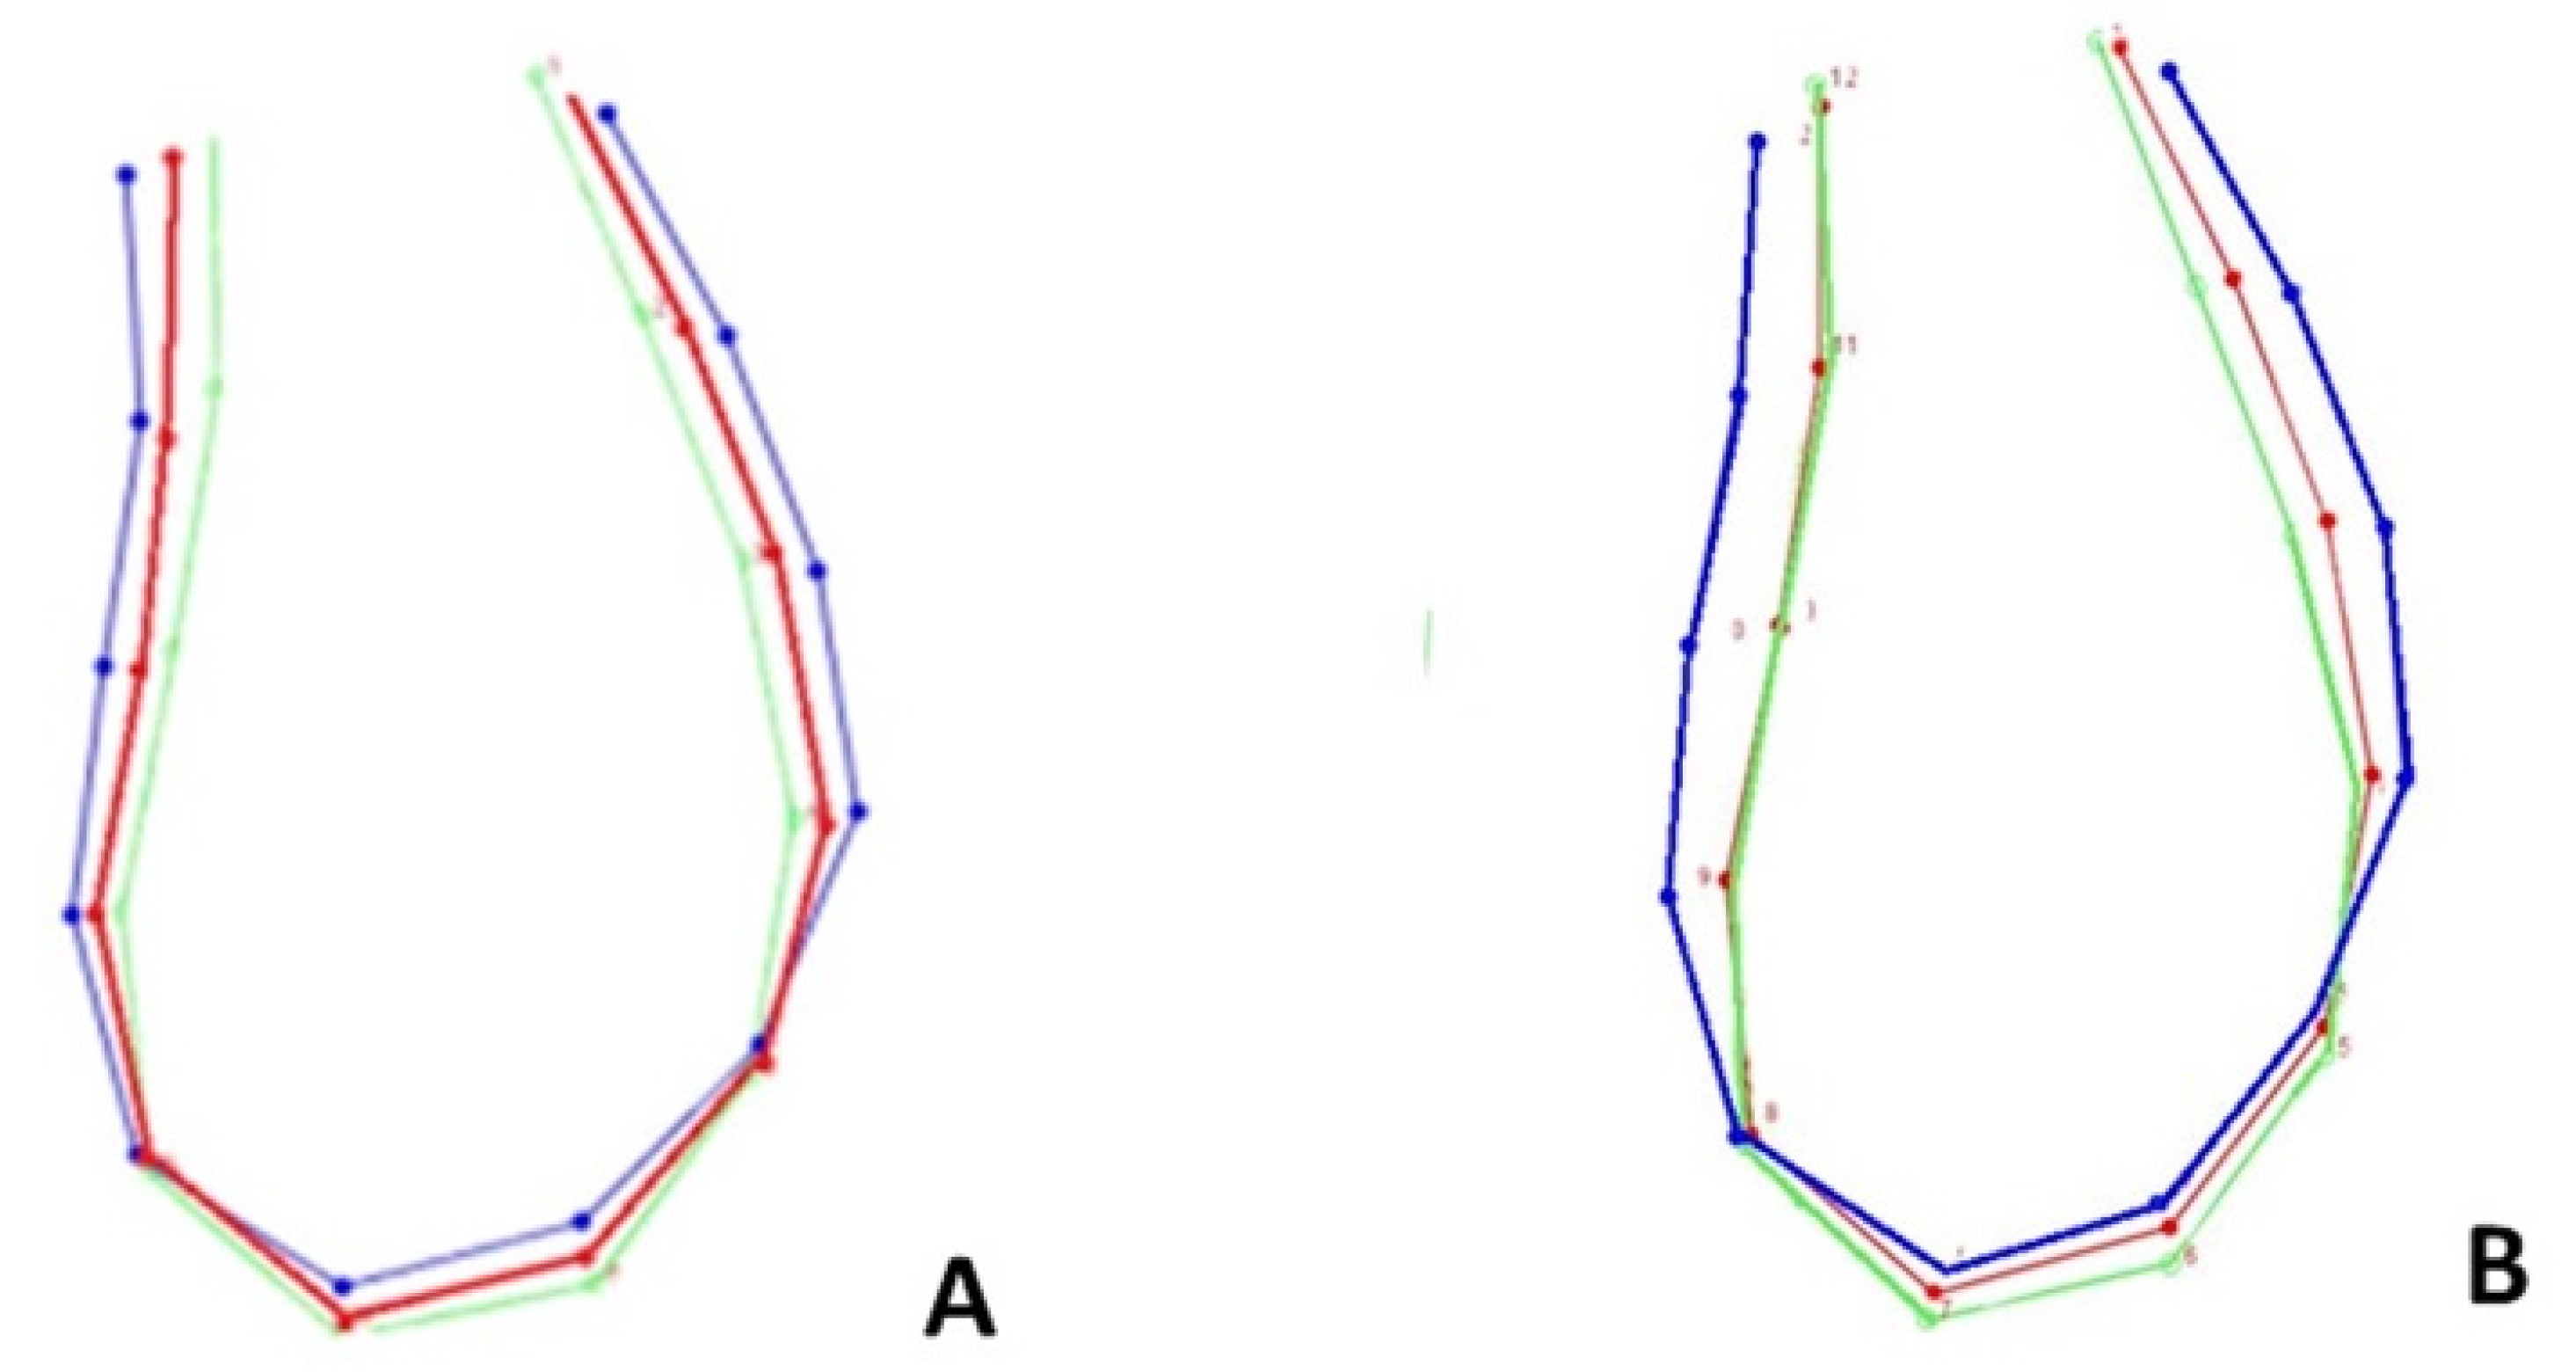

3.2. Age, Sex, and Form Correlation

4.2. Age, Sex, and Ms’Form Correlation